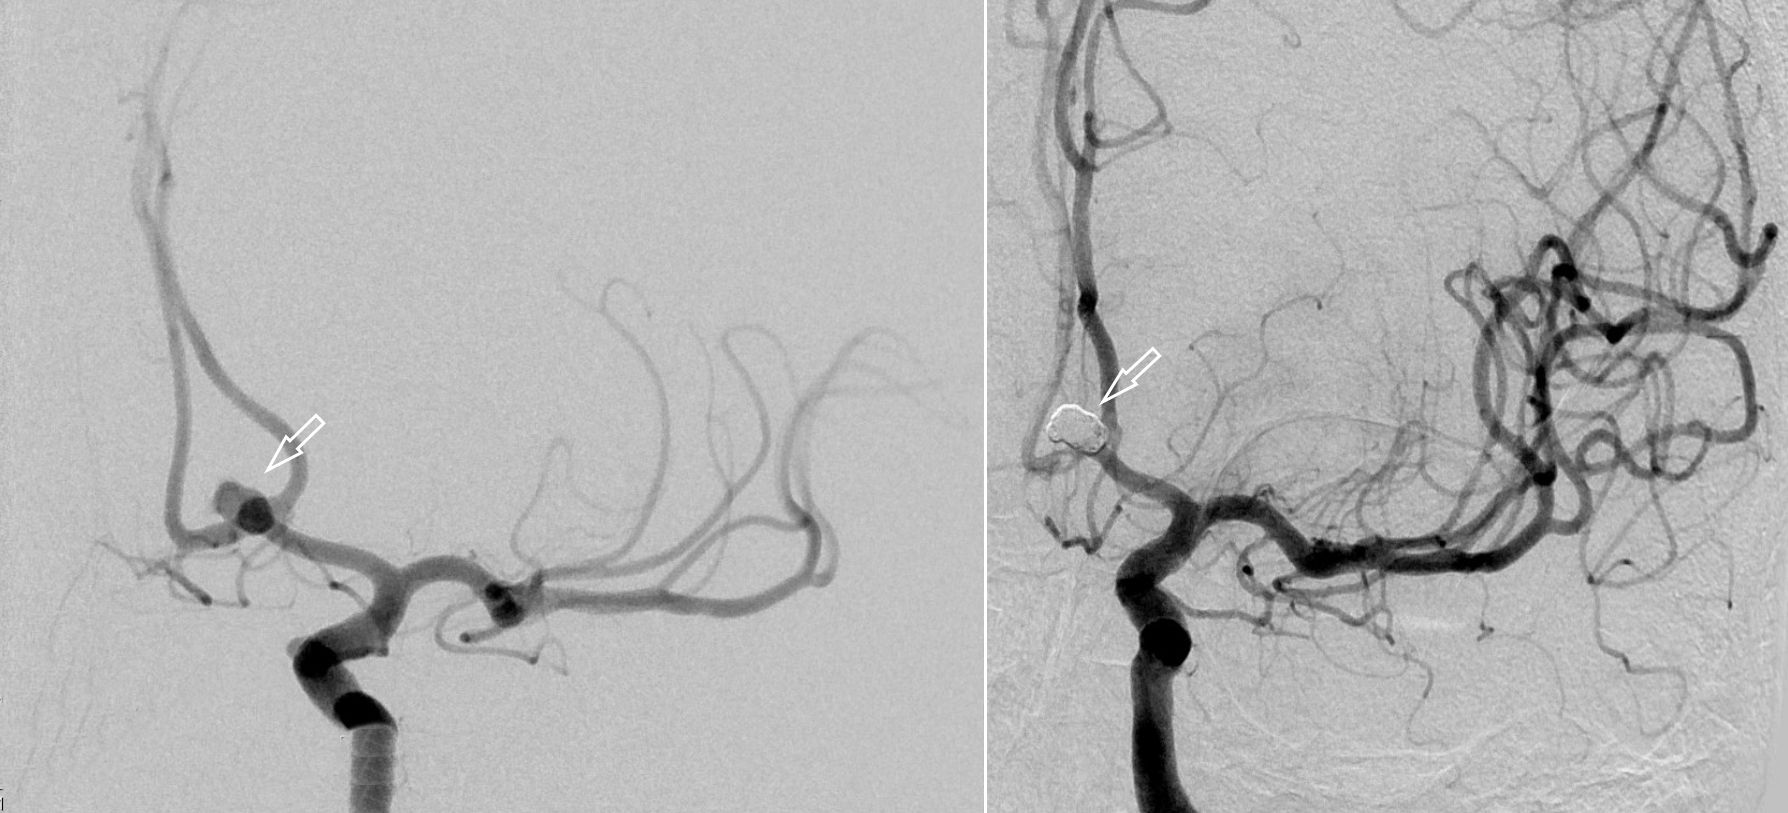

Als schnellste und sicherste Maßnahme gilt das craniale Computertomogramm (CCT). Hier lässt sich eine frische SAB meist zuverlässig darstellen, wobei auch bereits richtungsweisende Befunde, wie das Ausmaß der Blutung und eine eventuelle Lokalisation eines möglichen Aneurysmas bestimmt werden können. Darüber hinaus kann ein Angio-CCT, bei dem zusätzlich Kontrastmittel verabreicht wird und dann die intrazerebralen Blutgefäße gesondert rekonstruiert und dargestellt werden, weitere Informationen liefern. Der sogenannte “Goldstandard” zur Diagnose zerebraler Gefäßmissbildungen ist jedoch die zerebrale Angiographie. Dabei wird mit Hilfe eines speziellen Katheters über die Leisten- oder Armarterie Kontrastmittel gegeben und die zerebralen Blutgefäße hoch selektiv dargestellt. Sollten sich auf dem initialen CCT Zeichen des Hirnwasseraufstaus zeigen, der durch ein Verstopfen der Abflusskanäle durch das neu aufgetretene Blut bedingt ist, ist oft die Anlage einer Hirnwasserableitung nach außen notwendig (externe Ventrikeldrainage).

CT Bildgebung der klassischen subarachnoidalen Blutverteilung nach SAB